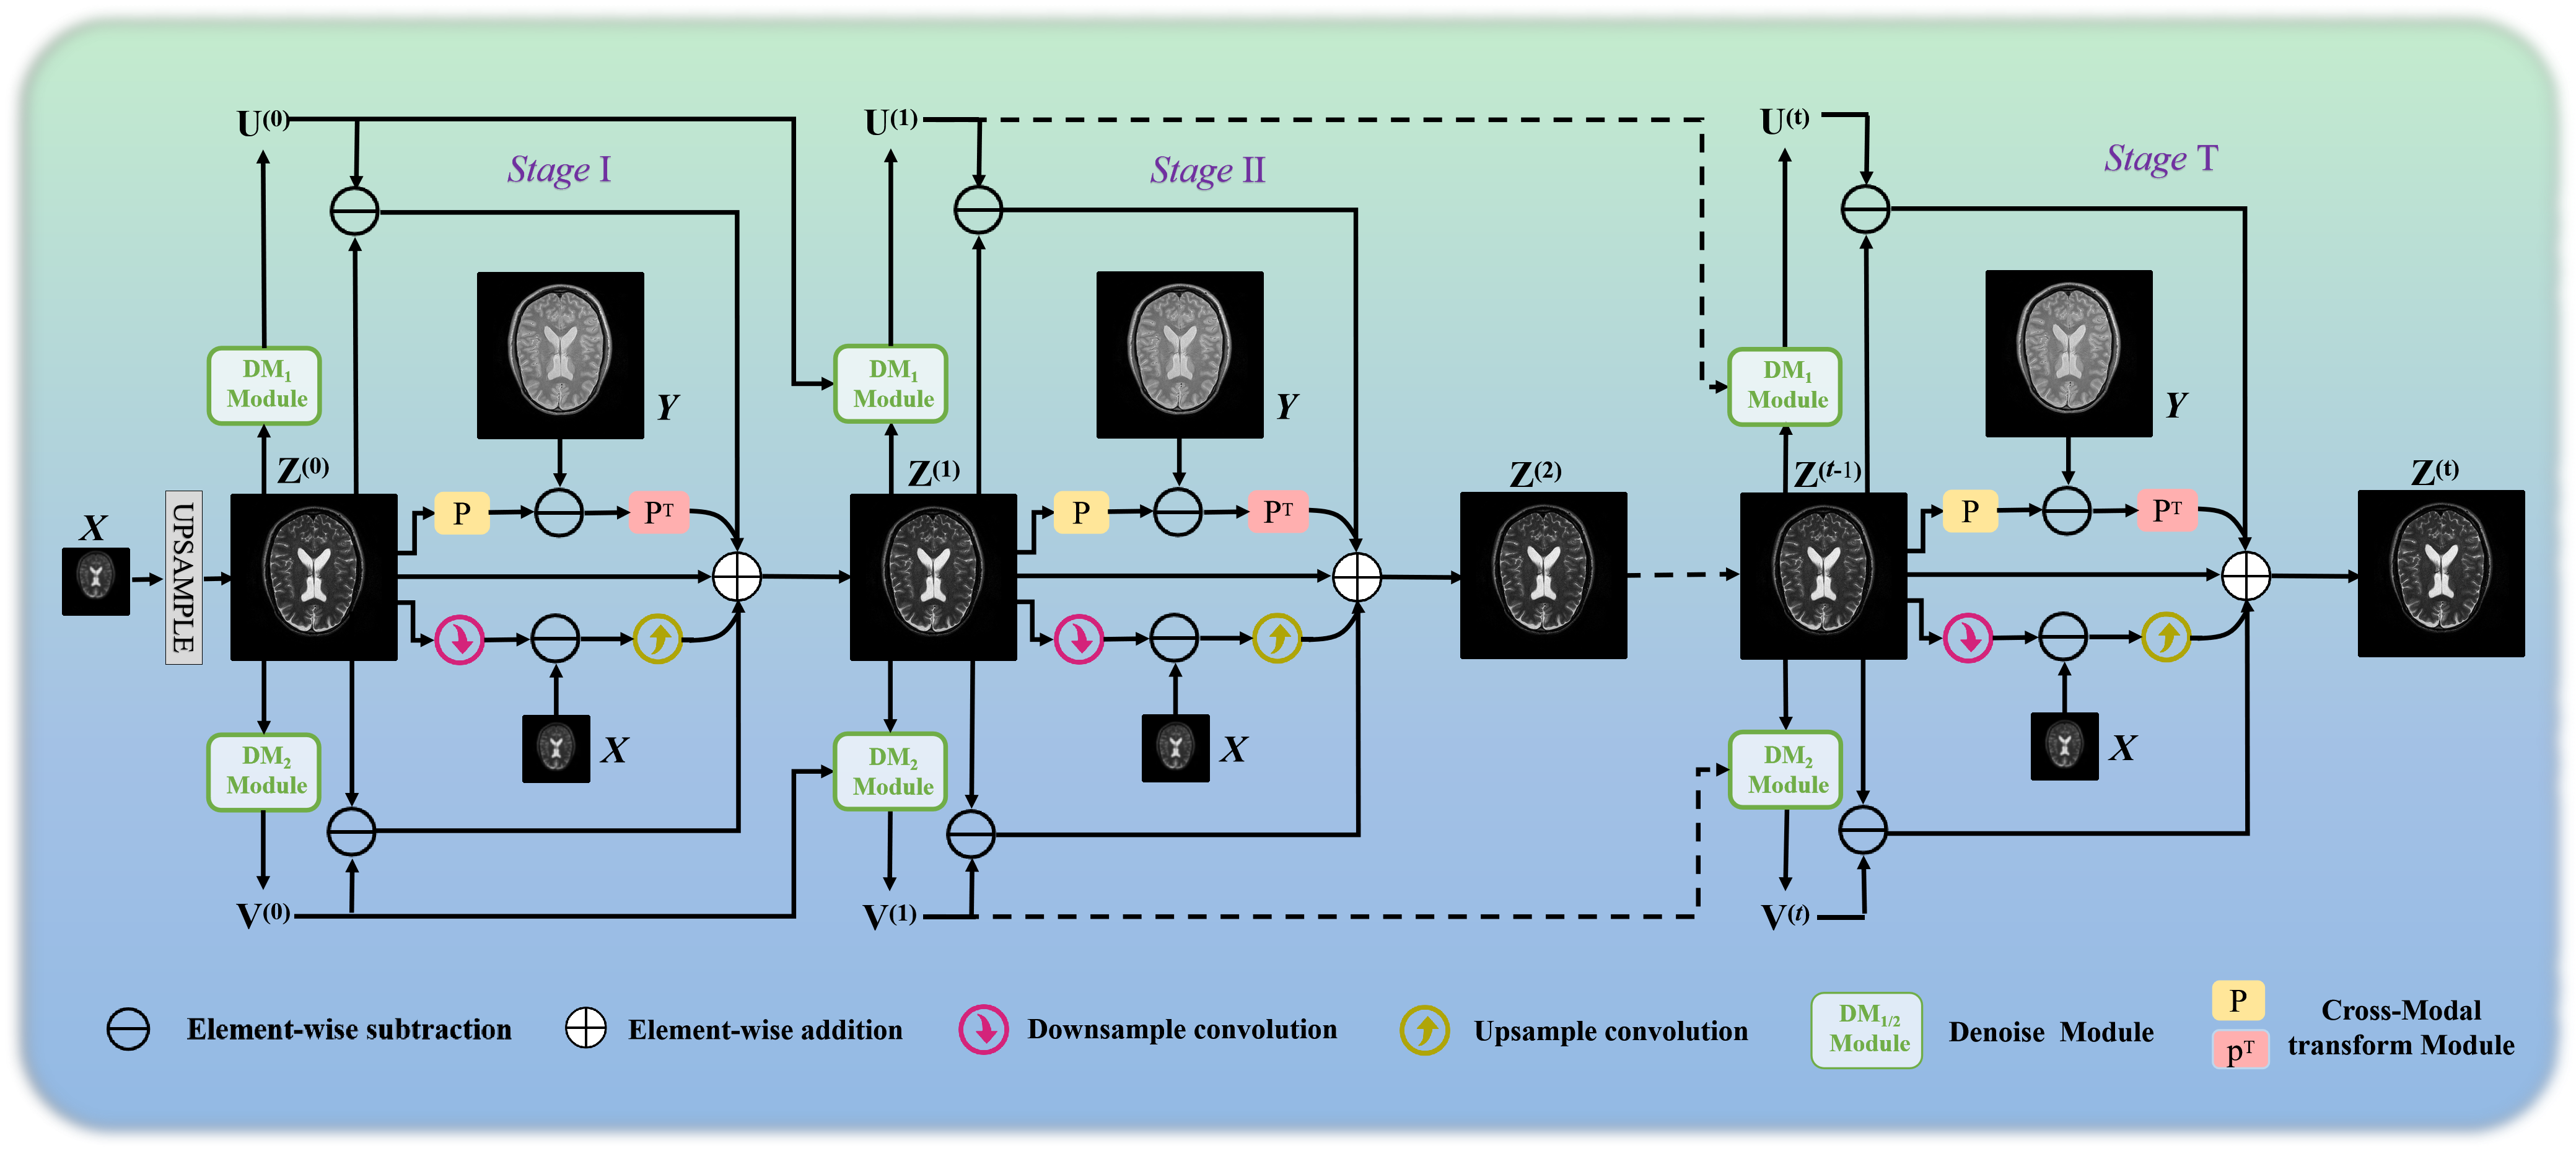

The overall network architecture of the MGDUN is shown in Fig. 1, which contains stages that are intentionally designed to correspond to iterations in the PGD optimization algorithm. Each stage of MGDUN consists of three specified network modules, containing a deep denoising module for denoising and updating for auxiliary variables, a cross-modal transform Module for cross-modal transform function, and a reconstruction module for reconstruction and updating for . We will elaborate on each module next.

3.3.2. The deep denoising module

The design of deep denoising modules corresponds to the computing the updated estimate and in Eq. 3.2.2 and Eq. 3.2.2, respectively. In general, any existing image denoising network can be used as the denoising module here.

As shown in Fig. 1, the intermediate estimates and are fed into the proximal operator after weighting with the intermediate estimate for further refinement. In this paper, we have adopted a variant of U-net as the backbone of the deep denoising module. Other more effective networks for medical image denoising can be also adopted. The U-net denoising network consists of an encoder and a decoder. As shown in Fig. 2(a), the encoder consists of four encoding blocks, which contain two convolutional layers with kernels and ReLU nonlinearity. Corresponding to the encoder, the decoder also consists of four decoding blocks, which contain two convolutional layers with kernels and ReLU nonlinearity. Instead of predicting the refine auxiliary various directly, we enable the denoising module to predict the residual by adding a skip connection from the input to the output. To reduce the number of network parameters and the effect of overfitting, we opt to enforce all denoising modules sharing the same network parameters.

3.3.3. Cross-Modal Transform Module

Noted that Eq. 16 involves the cross-modal transform matrix and that are expensive to calculate. We find that and perform a cross-modal transform operation, and the two processes are inverted: one from the target contrast image to the guide contrast image, and the other from the guide contrast image to the target contrast image. The process can be formulated as:

As a result, we design cross-modal transform modules using the principle of invertible neural networks (INNs). INNs have been adopted in various inference tasks and achieved excellent performance due to their flexibility (Kingma et al., 2016; Lu et al., 2021). We formulate an INN architecture design to serve as cross-modal transform operation. It consists of two pixel shuffling layers (Dinh et al., 2016) and several INN blocks. As shown in Figure 2(b), relevant invertible modules are embedded in the cross-modal transform module.

For the t-th stage, given an evaluation HR MRI () to be refined, we first put it to one pixel shuffling layer for changing dimension, then pass through several INN blocks to execute the cross-modal transform function, and finally restore the original dimension through the other pixel shuffling layer.

For the forward operation, one pixel shuffling layer executes dimension addition first. Then the input () is divided into () and () along the channel axis, and the corresponding cross-modal transform output is and (two components of ). This process corresponds to the operation of cross-modal transform matrix , in which an INN block can be expressed as :

where , and are arbitrary functions, is Exponential functions, and is the Hadamard product.

3.3.4. Reconstruction Module

The design of the reconstruction module corresponds to the update of intermediate evaluated as described in Eq. 16. With the output of denoising modules (, ), the evaluated HR image , the LR MRI and the guide image , we can reconstruct the updated image . The architecture of the reconstruction module is shown in Fig. 1 and Eq. 16, which still involve the degradation operations ( and ). The pair of operation and can be implemented by up-sampling and down-sampling layers for modeling capability.

The operators and are simulated using a convolution network layer respectively. Specifically, is simulated by a network called down-sampling-blocks () consisting of a convolutional layer with kernels and 64 channels, one max pool layer to decrease the spatial resolution, and two convolutional layers with kernels for reprojection to the original dimension (as shown in Figure 2(c)). Similarly, the is simulated by a network call Up-sampling-blocks () consisting of a convolutional layer with kernels and 64 channels, and one upsample layer to increase the spatial resolution and two convolutional layers with kernels for reprojection to the original dimension as shown in Figure 2(d).